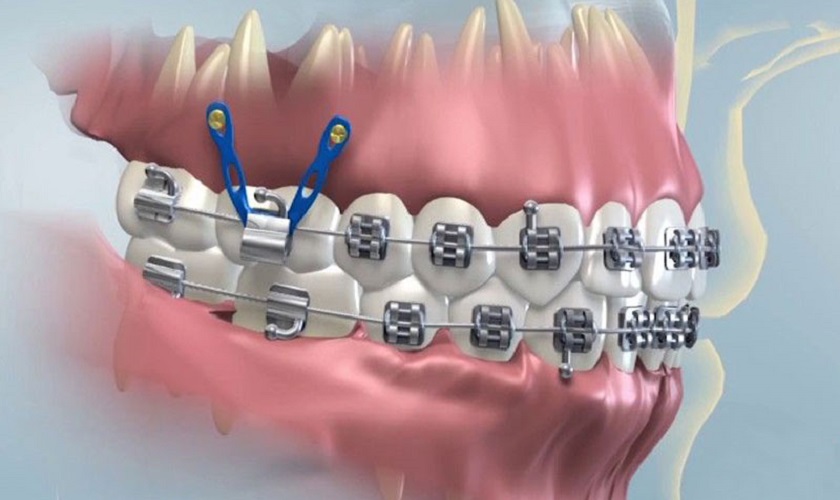

Với những bất lợi về sức khỏe răng miệng đã nêu trên, câu trả lời từ góc độ chuyên môn nha khoa là: Có, nên niềng răng khểnh. Niềng răng không chỉ giúp sắp xếp các răng về đúng vị trí trên cung hàm, cải thiện thẩm mỹ nụ cười mà quan trọng hơn là khôi phục chức năng ăn nhai, giảm thiểu nguy cơ mắc các bệnh lý răng miệng và bảo vệ sức khỏe tổng thể.

Niềng răng sẽ giúp:

- Cải thiện vệ sinh răng miệng: Khi răng thẳng hàng, việc vệ sinh trở nên dễ dàng hơn rất nhiều, giảm nguy cơ sâu răng và viêm nướu.

- Tối ưu hóa chức năng ăn nhai: Đảm bảo răng nanh thực hiện đúng vai trò, giúp nghiền nát thức ăn hiệu quả hơn.

- Ngăn ngừa các vấn đề về khớp thái dương hàm: Đưa khớp cắn về trạng thái lý tưởng, giảm áp lực lên khớp.

- Tăng tính thẩm mỹ: Mang lại nụ cười đều đặn, hài hòa, giúp chủ nhân tự tin hơn trong giao tiếp và cuộc sống.